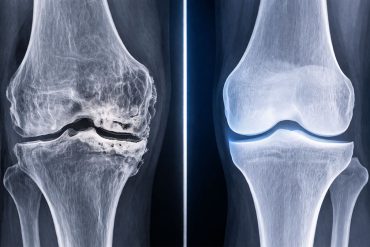

Osteoarthritis is one of the most common and debilitating conditions associated with aging and injury, affecting roughly 20 percent of the U.S. population. For decades, treatment options have been limited. Most approaches focus on managing pain or, in severe cases, replacing the joint entirely. Now, a new study led by Stanford Medicine offers a fundamentally different path forward.

Researchers have discovered that blocking a specific enzyme, known as 15-hydroxy prostaglandin dehydrogenase, or 15-PGDH, can actually reverse cartilage loss. This finding opens the door to therapies that do not just slow the disease but potentially restore damaged tissue.

The implications are significant. Current osteoarthritis treatments do not reverse damage. This approach could change that by directly targeting a mechanism linked to aging itself. Researchers describe 15-PGDH as a “gerozyme,” an enzyme that drives tissue aging.

By inhibiting this enzyme, the study concludes that cartilage regeneration can occur not only in animal models but also in human tissue. This positions the therapy as “a new therapeutic approach for OA that is readily amenable to translation to the clinic.”

If these findings hold up in further trials, they could mark a turning point in how joint disease is treated. Instead of managing decline, medicine may soon be able to restore what was lost.